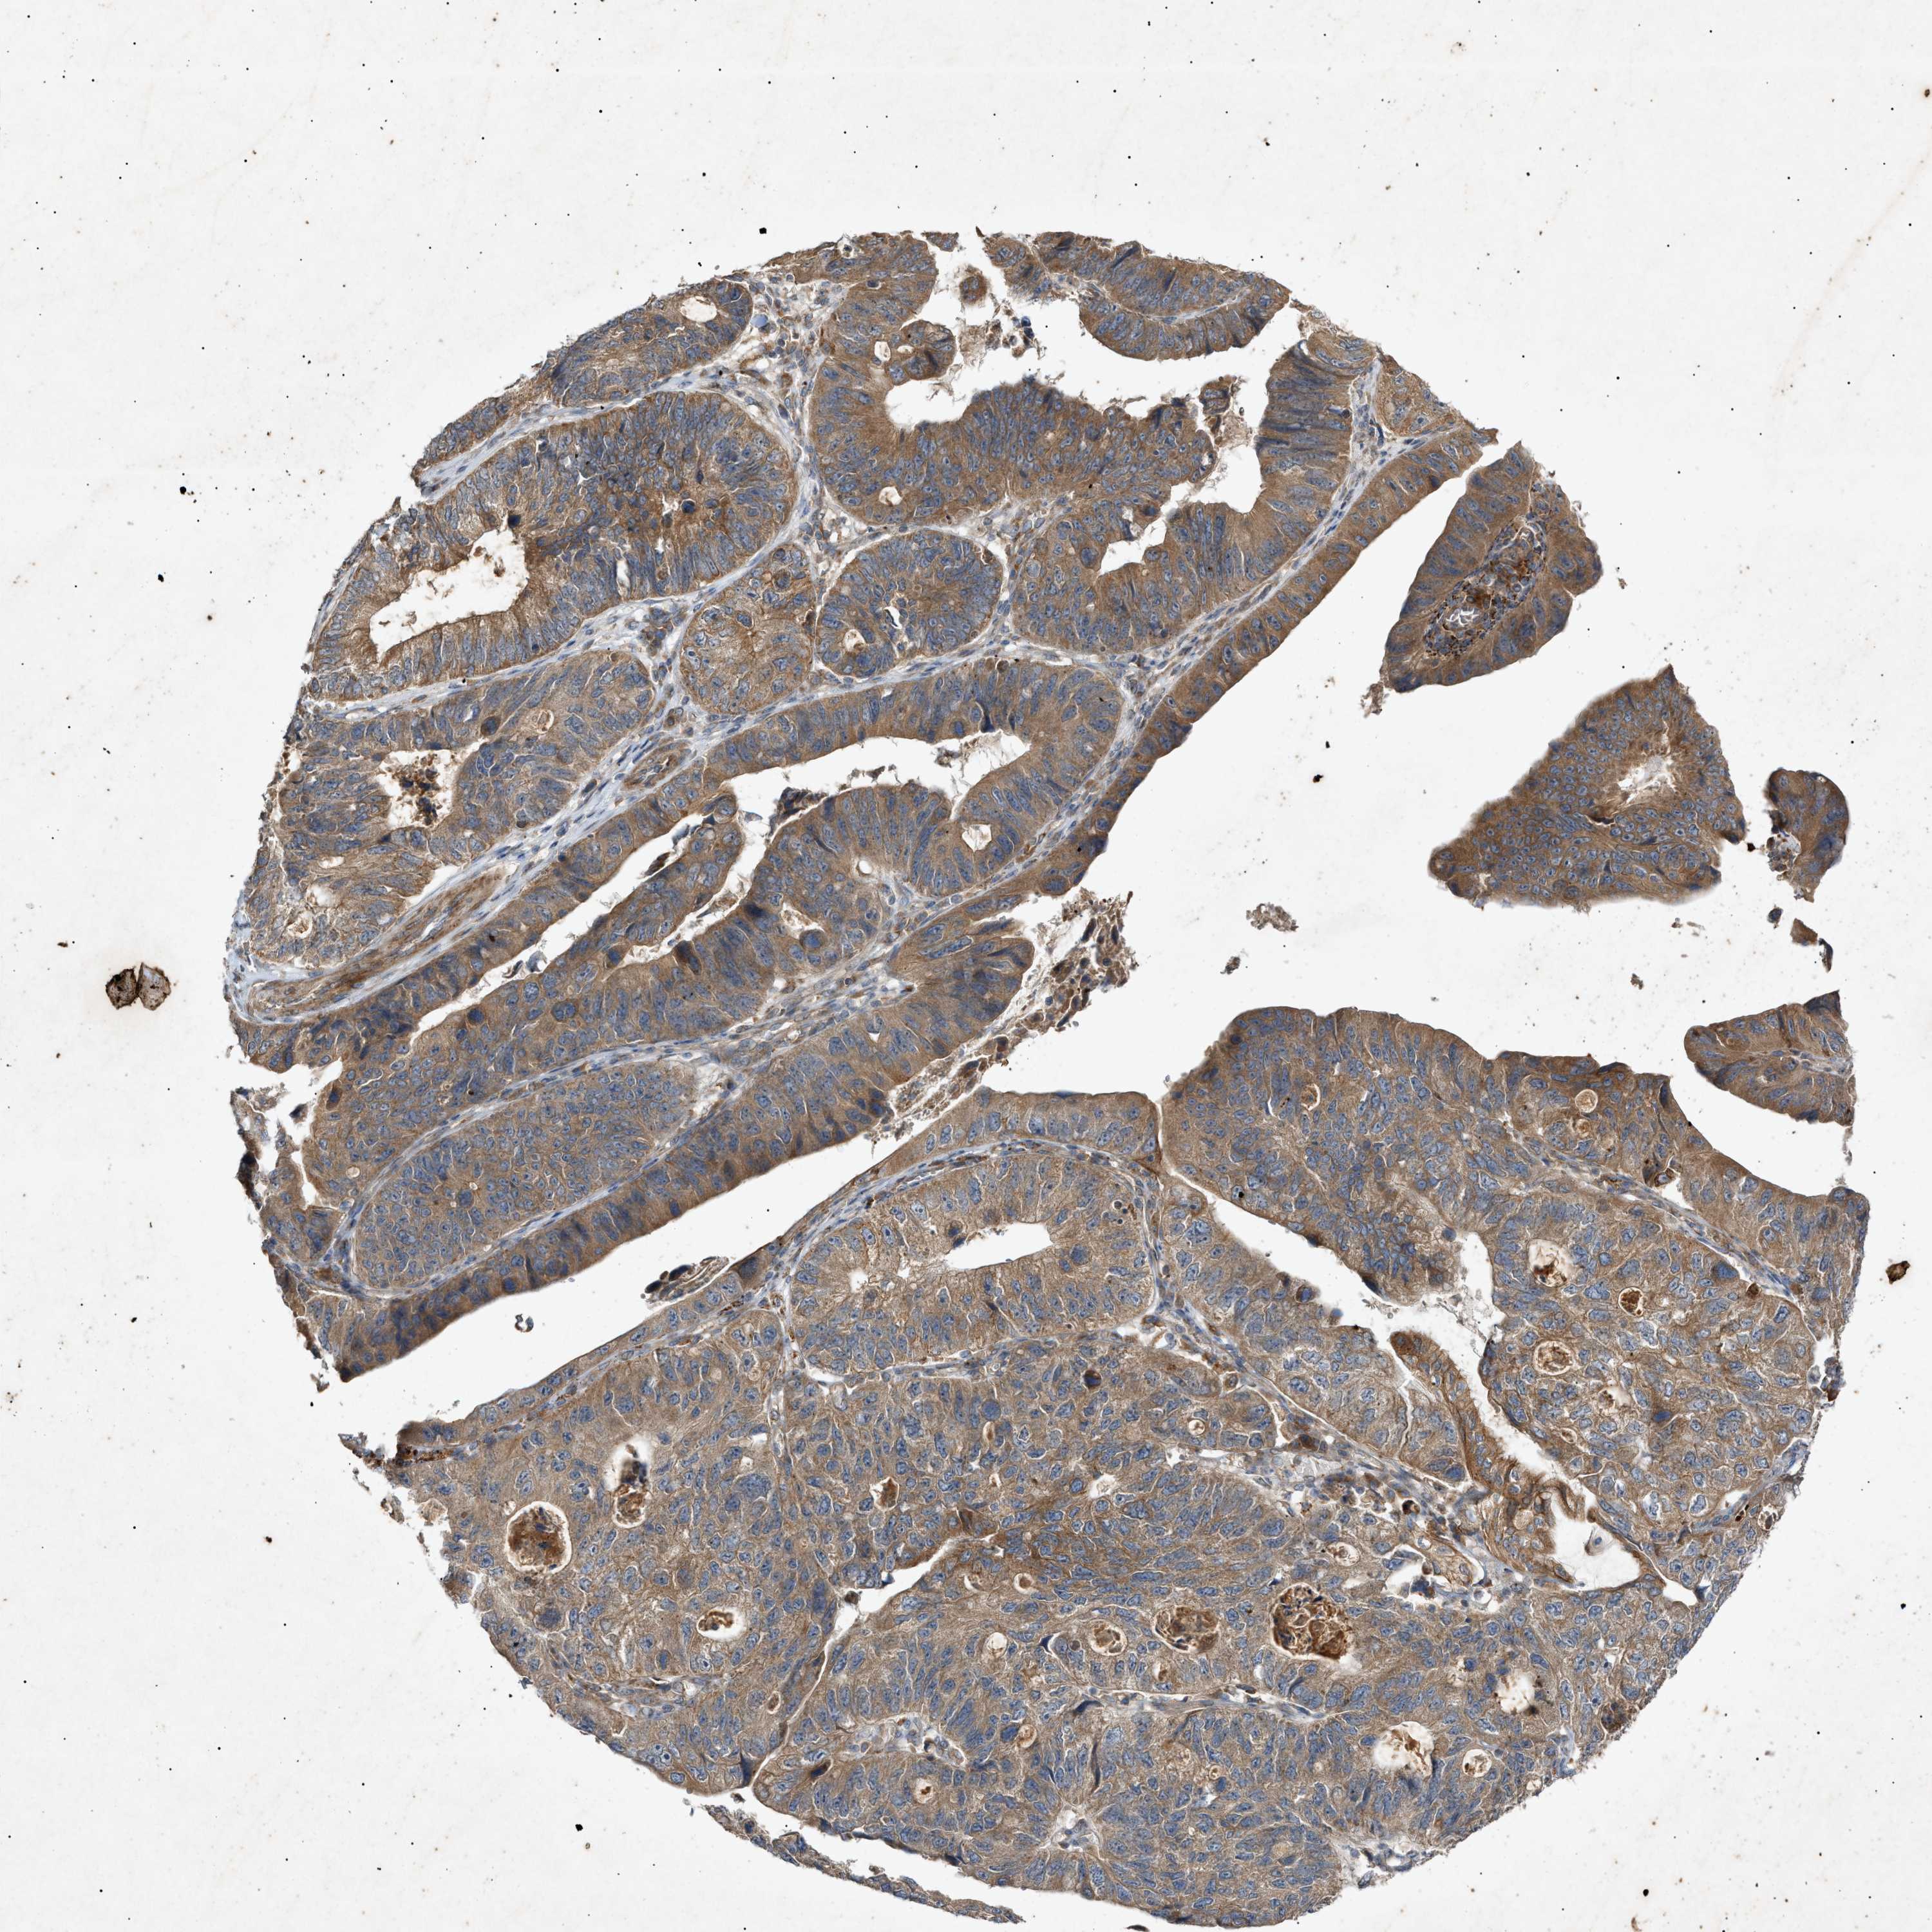

STOMACH CANCER - Protein expressioni

A mouse-over function shows sample information and annotation data. Click on an image to view it in a full screen mode. Samples can be filtered based on level of antibody staining by selecting one or several of the following categories: high, medium, low and not detected. The assay and annotation is described here.

Note that samples used for immunohistochemistry by the Human Protein Atlas do not correspond to samples in the TCGA dataset.

Antibody stainingi

Antibody staining in the annotated cell types in the current human tissue is reported as not detected, low, medium, or high, based on conventional immunohistochemistry profiling in selected tissues. This score is based on the combination of the staining intensity and fraction of stained cells.

Each image is clickable and will lead to virtual microscopy that enables deeper exploration of all samples and also displays staining intensity scores, fraction scores and subcellular localization as well as patient and tissue information for each sample.

Antibody HPA015971

Staining

High

Medium

Low

Not detected

Intensity

Strong

Moderate

Weak

Negative

Quantity

>75%

75%-25%

<25%

None

Location

Nuclear

Cytoplasmic/membranous

Cytoplasmic/membranous,nuclear

Adenocarcinoma, NOS